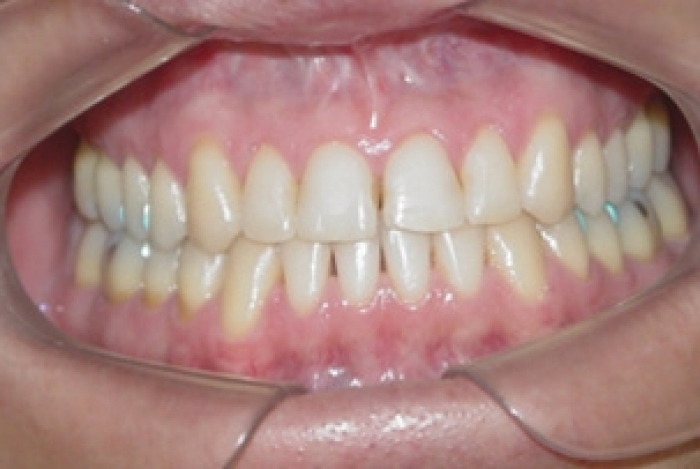

Mordida inicial

Mordida após a cirurgia

Mordida final após a remoção do aparelho